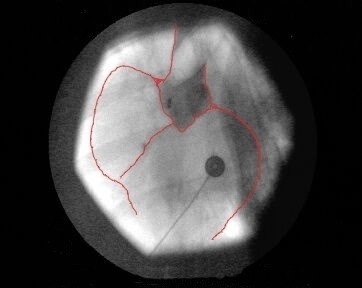

Als Referenz für die Darstellungsqualität wurden jeweils Koronarangiographien der Herzkranzgefäße in konventioneller Methode von einem Kardiologen durchgeführt [siehe Bild 2]. Es konnte gezeigt werden, dass die neuartige Methode einer indirekten Koronarangiographie in jedem modernen Herzkatheterlabor ohne zusätzliche Investitionen praktikabel ist. In den Versuchen gelang eine überzeugende gleichzeitige Darstellung beider Herzkranzgefäße [siehe Bild 1]. Weiterhin konnte auch die linke Herzkammer in gewohnter Qualität abgebildet werden.